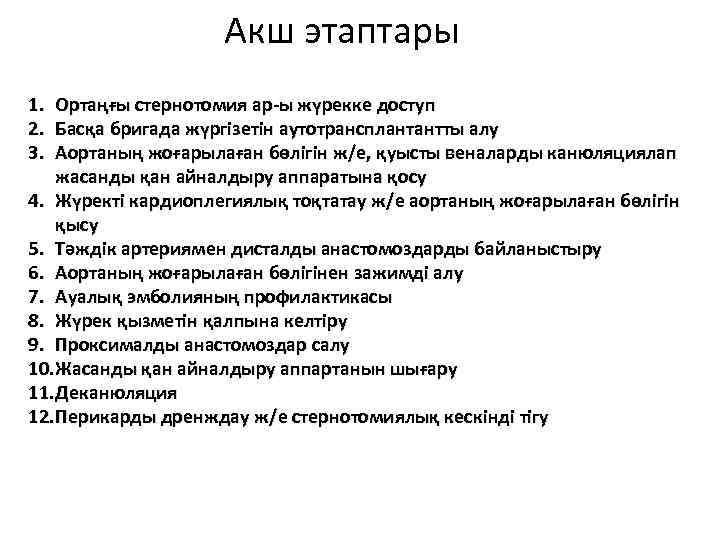

Акш этаптары 1. Ортаңғы стернотомия ар-ы жүрекке доступ 2. Басқа бригада жүргізетін аутотрансплантантты алу 3. Аортаның жоғарылаған бөлігін ж/е, қуысты веналарды канюляциялап жасанды қан айналдыру аппаратына қосу 4. Жүректі кардиоплегиялық тоқтатау ж/е аортаның жоғарылаған бөлігін қысу 5. Тәждік артериямен дисталды анастомоздарды байланыстыру 6. Аортаның жоғарылаған бөлігінен зажимді алу 7. Ауалық эмболияның профилактикасы 8. Жүрек қызметін қалпына келтіру 9. Проксималды анастомоздар салу 10. Жасанды қан айналдыру аппартанын шығару 11. Деканюляция 12. Перикарды дренждау ж/е стернотомиялық кескінді тігу

Акш этаптары 1. Ортаңғы стернотомия ар-ы жүрекке доступ 2. Басқа бригада жүргізетін аутотрансплантантты алу 3. Аортаның жоғарылаған бөлігін ж/е, қуысты веналарды канюляциялап жасанды қан айналдыру аппаратына қосу 4. Жүректі кардиоплегиялық тоқтатау ж/е аортаның жоғарылаған бөлігін қысу 5. Тәждік артериямен дисталды анастомоздарды байланыстыру 6. Аортаның жоғарылаған бөлігінен зажимді алу 7. Ауалық эмболияның профилактикасы 8. Жүрек қызметін қалпына келтіру 9. Проксималды анастомоздар салу 10. Жасанды қан айналдыру аппартанын шығару 11. Деканюляция 12. Перикарды дренждау ж/е стернотомиялық кескінді тігу